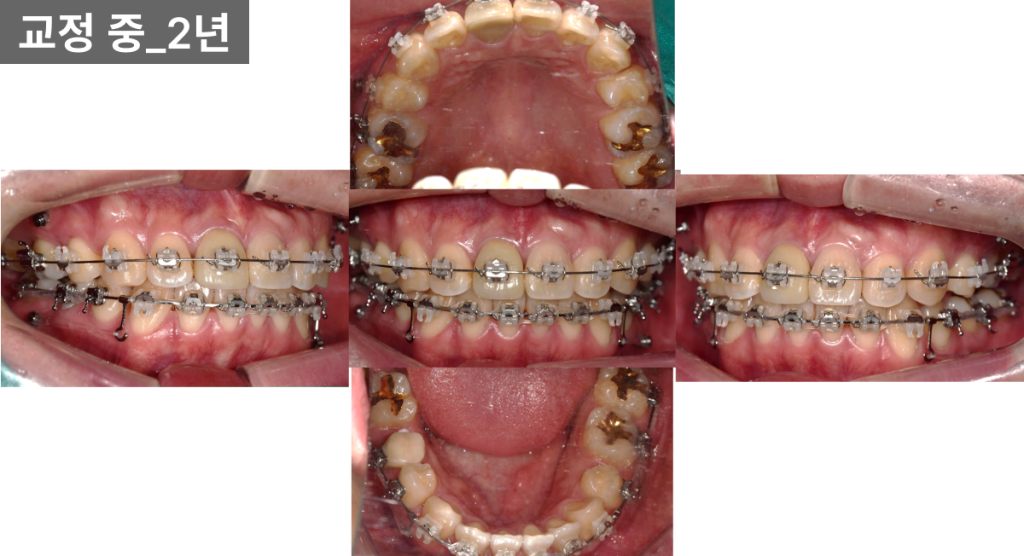

후반 단계 (약 2년)

상악은 재배열 과정에서

일시적으로 공간이 다시 벌어졌으나,

하악은 대부분 공간이 닫힌 상태였습니다.

오른쪽은 크라운 보철을 고려해

일부 공간을 의도적으로 남겨두었고,

교합 역시 점차 안정화되었습니다.

이 과정에서 상악동 위치 차이로 인해

왼쪽 치아 이동 속도가

다소 느린 점도 함께 확인되었습니다.